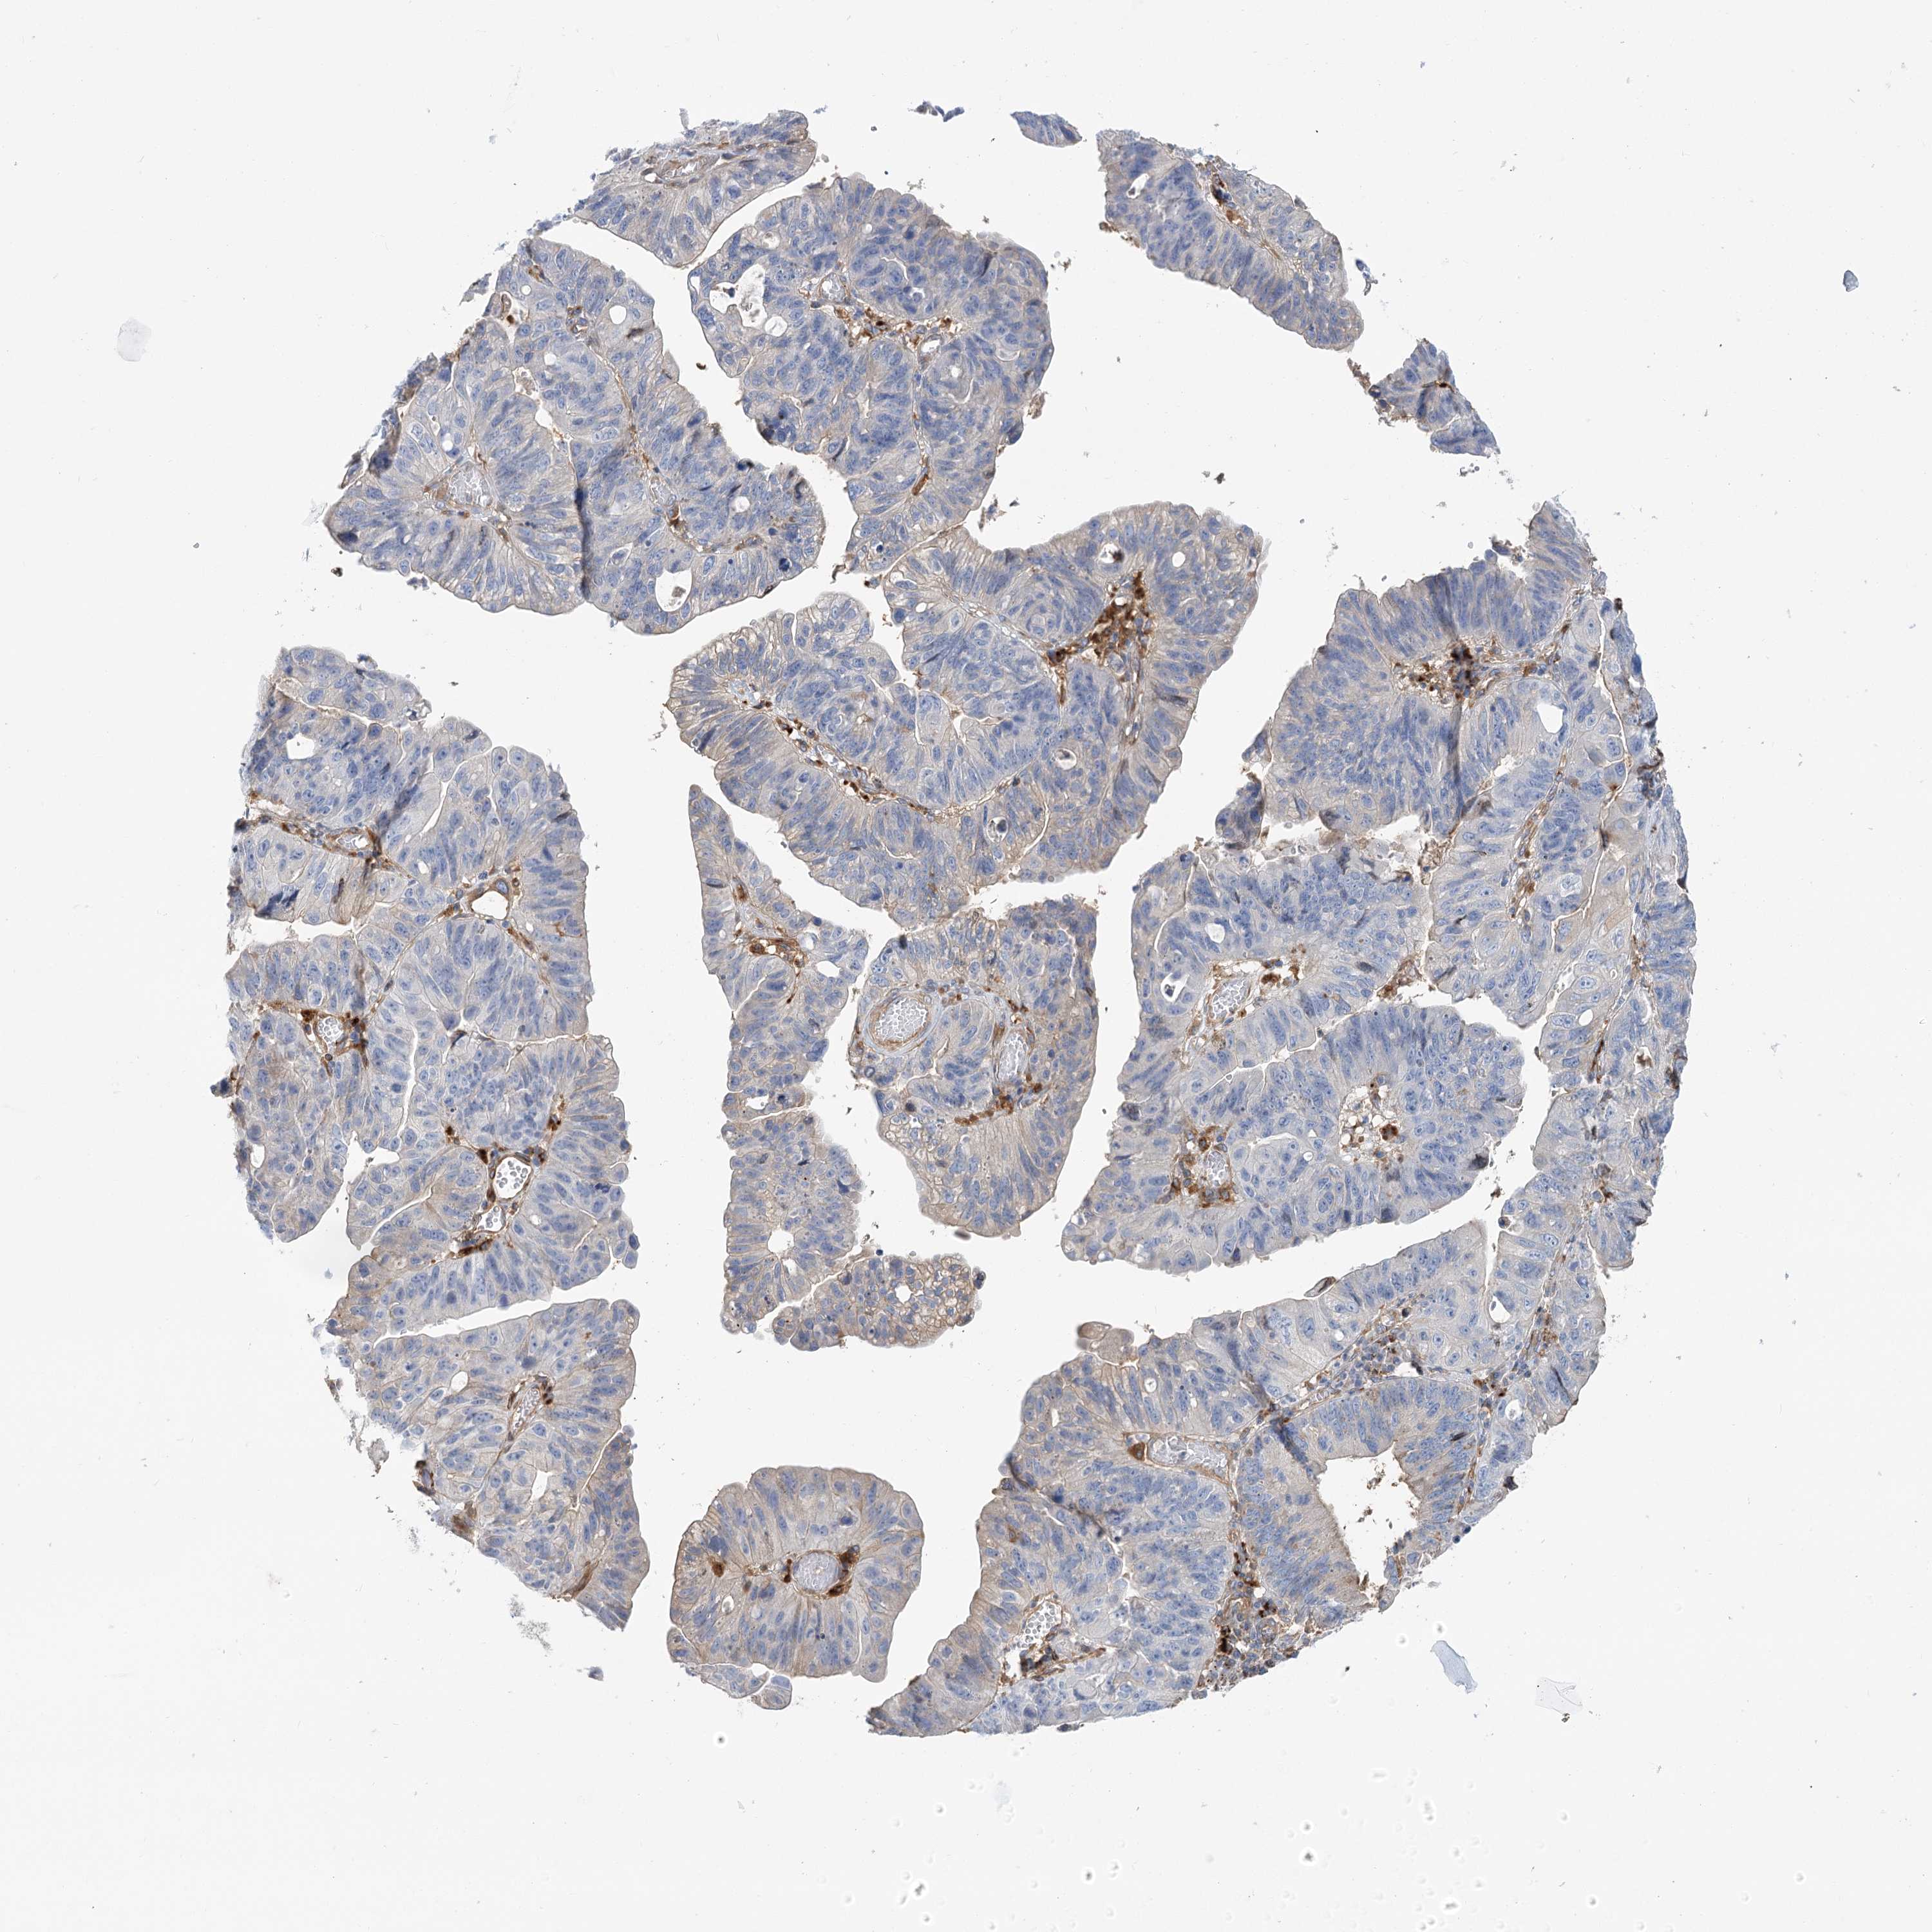

STOMACH CANCER - Protein expressioni

A mouse-over function shows sample information and annotation data. Click on an image to view it in a full screen mode. Samples can be filtered based on level of antibody staining by selecting one or several of the following categories: high, medium, low and not detected. The assay and annotation is described here.

Note that samples used for immunohistochemistry by the Human Protein Atlas do not correspond to samples in the TCGA dataset.

Antibody stainingi

Antibody staining in the annotated cell types in the current human tissue is reported as not detected, low, medium, or high, based on conventional immunohistochemistry profiling in selected tissues. This score is based on the combination of the staining intensity and fraction of stained cells.

Each image is clickable and will lead to virtual microscopy that enables deeper exploration of all samples and also displays staining intensity scores, fraction scores and subcellular localization as well as patient and tissue information for each sample.

Adenocarcinoma, NOS